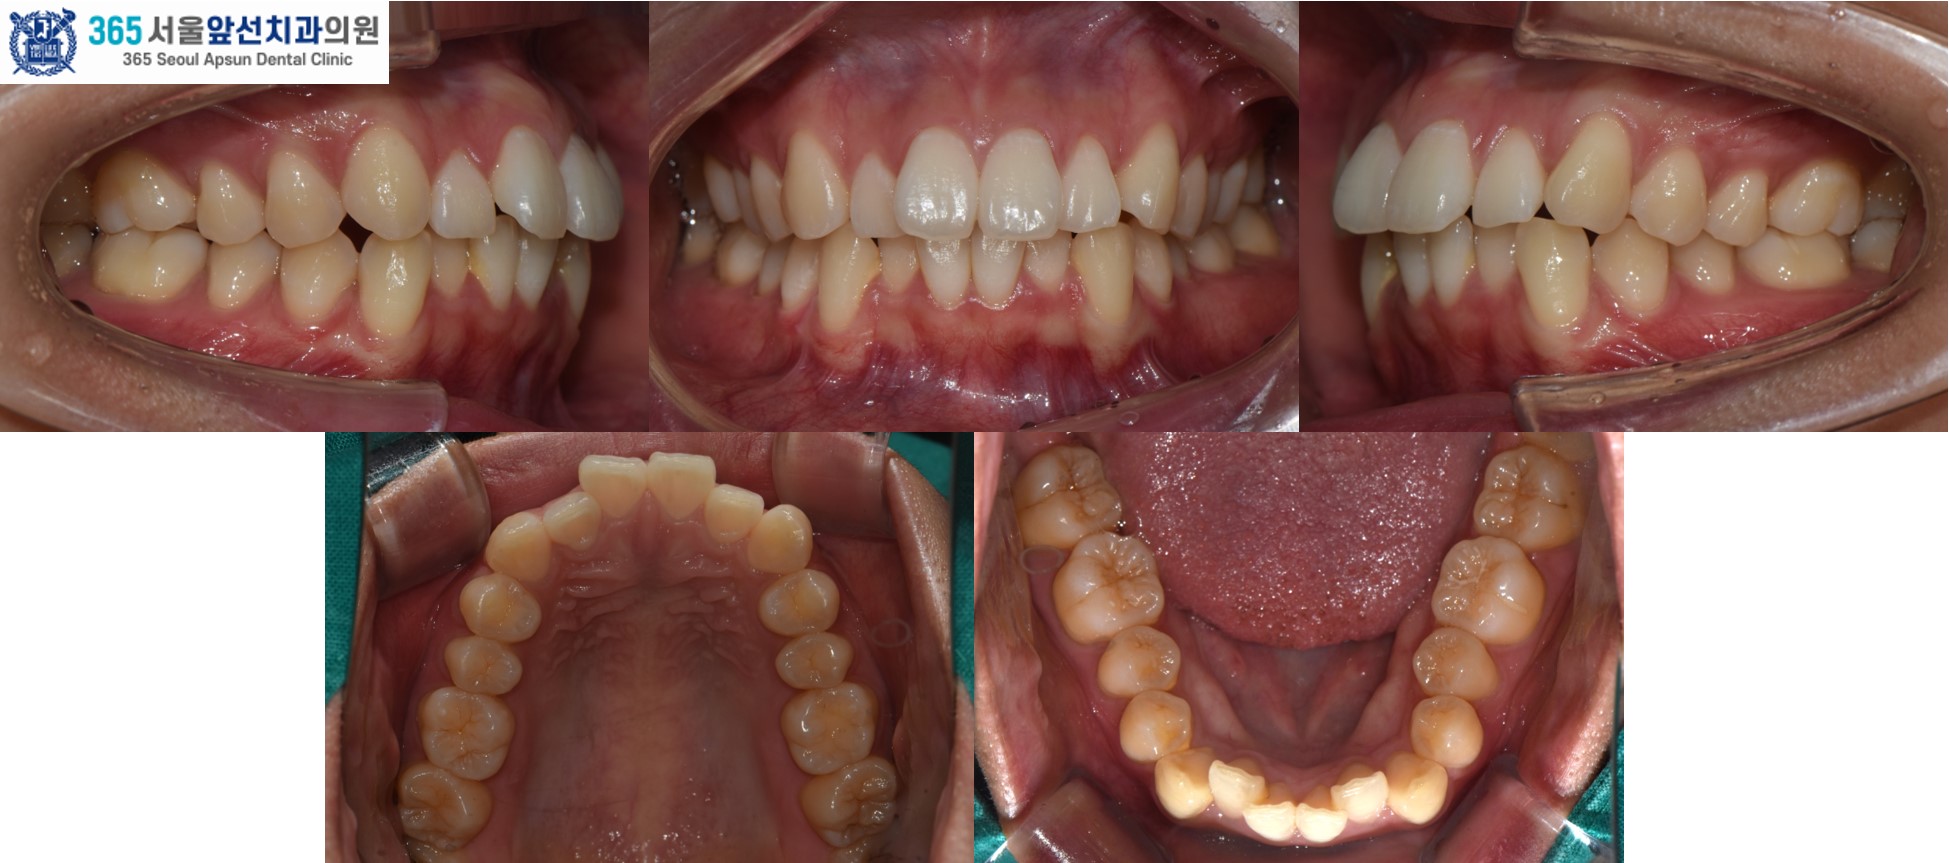

(그림1) 촬영일자 2025.02.25. / 2025.11.06.

앞니의 비뚤한 치열을 고민으로 내원하신 20대 여성 환자 분의 증례를 소개드리겠습니다. 치료 전의 모습입니다. 상,하악 치열 각각 3.1mm, 2.9mm 의 필요 공간이 있는 중등도의 총생(Crowding)이 관찰됩니다. (그림2) 촬영일자 2025.02.25.